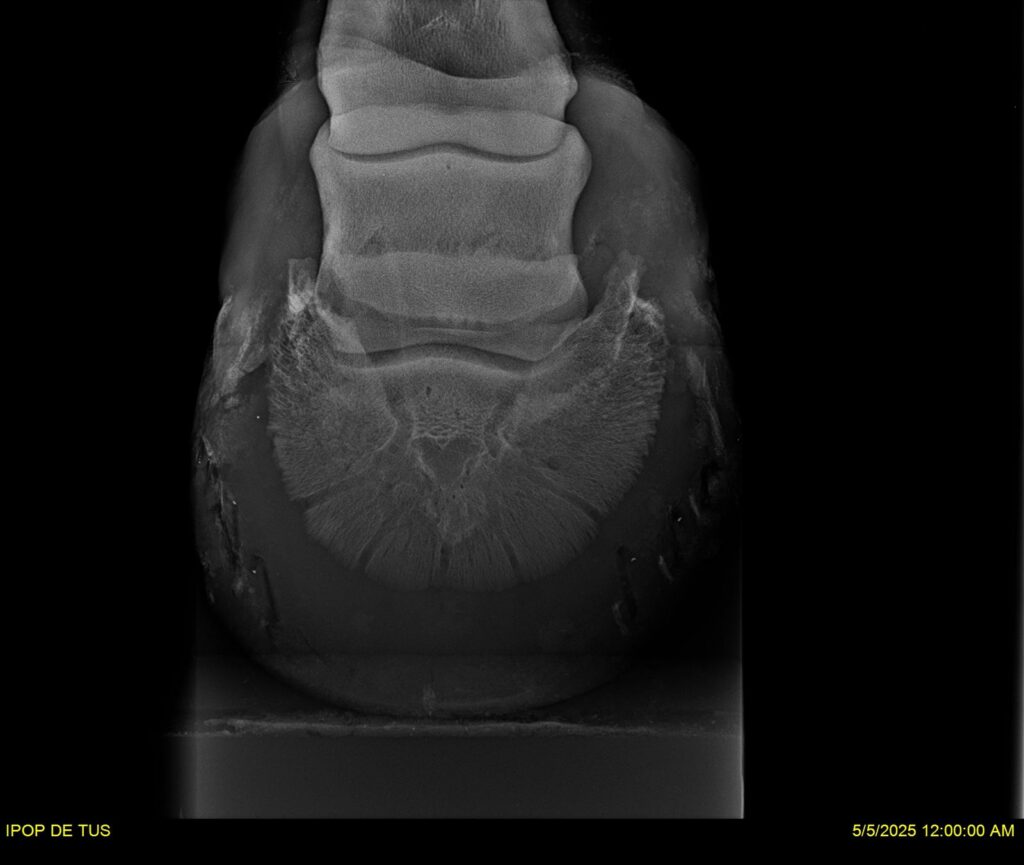

IPOP DE TUS, selle français, hongre, prendra 8 ans en 2026. LIFESTYLE x EROTICBLUS MONTOIS. Sans faute sur 125 et 130. Gentil cheval, respectueux avec des moyens et de la force. Transport OK, maréchalerie OK (pieds nus), santé RAS, Bilan clichés radios + clinique OK.

RADIOS ET CLINIQUE